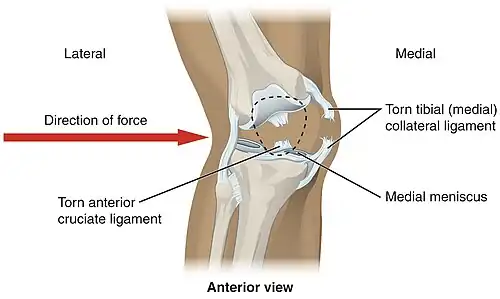

In sports that place great pressure on the knees, especially with twisting forces, it is common to tear one or more ligaments or cartilages. Some of the most common knee injuries are those to the medial side: medial knee injuries.[32]

Anterior cruciate ligament injury

The anterior cruciate ligament is the most commonly injured ligament of the knee. The injury is common during sports. Twisting of the knee is a common cause of over-stretching or tearing the ACL. When the ACL is injured a popping sound may be heard, and the leg may suddenly give out. Besides swelling and pain, walking may be painful and the knee will feel unstable. Minor tears of the anterior cruciate ligament may heal over time, but a torn ACL requires surgery. After surgery, recovery is prolonged and low impact exercises are recommended to strengthen the joint.[33]

The knee is stabilized by a pair of cruciate ligaments. These ligaments are both extrasynovial, intracapsular ligaments.[20] The anterior cruciate ligament (ACL) stretches from the lateral condyle of femur to the anterior intercondylar area.[13] The ACL prevents the tibia from being pushed too far anterior relative to the femur.[13] It is often torn during twisting or bending of the knee.[21] The posterior cruciate ligament (PCL) stretches from medial condyle of femur to the posterior intercondylar area. This ligament prevents posterior displacement of the tibia relative to the femur.[13] Injury to this ligament is uncommon but can occur as a direct result of forced trauma to the ligament.

The medial collateral ligament (MCL a.k.a. "tibial") stretches from the medial epicondyle of the femur to the medial tibial condyle. It is composed of three groups of fibers, one stretching between the two bones, and two fused with the medial meniscus. The MCL is partly covered by the pes anserinus and the tendon of the semimembranosus passes under it.[10]: 206 It protects the medial side of the knee from being bent open by a stress applied to the lateral side of the knee (a valgus force).[10]: 206